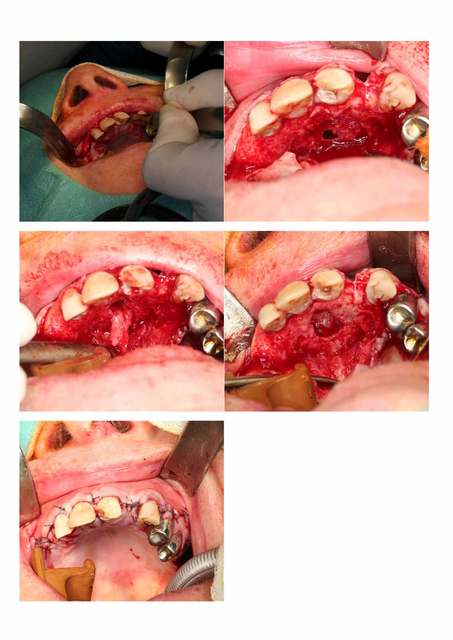

J'ai opéré une patiente pour 2 kystes l'un résiduel en position de 22 et l'autre naso-palatin.

Plutot rigolo d'avoir si proche 2 kystes si différents.

Pour le nasopalatin ce que l'on voit sur la photo c'est la muqueuse du plancher des fosses nasale.

Durée 1h00-1h15 mais faut dire que c'était sous AG.